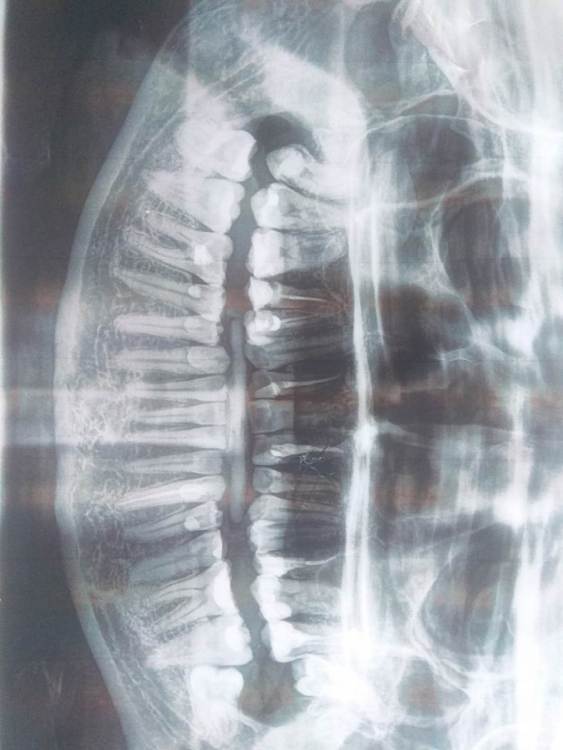

Primavera2023 Опубликовано 2 ноября, 2023 Поделиться Опубликовано 2 ноября, 2023 Возраст 32 года. Эти зубы не доставляют дискомфорта. Верхний полностью покрыт десной, нижний тоже был, пока один стоматолог летом щедро не резанул по десне, думая что режется 8 зуб, а причина боли была в кариесе зуба 3.6. Потом сделал рентген и удивился, что зуб дистопирован. Теперь боковая часть зуба 3.8. частично торчит из десны. На консультации в областном центре стоматолог хирург сказал - лучше удалить оба, а челюстно-лицевой хирург сказал, что если эти зубы не беспокоят то не надо трогать, воспаления там нет и могут быть осложнения, особенно с зубом 3.8., т.к. близко нерв. Ситуация с зубами у меня плохая - почти все зубы запломбированы, 9 депульпированы - большинство уже 7-8 лет назад. Возможно, в ситуации будущей потери некоторых зубов и эти две 8 могут быть мне полезны? Сверху зуб 2.7 давно депульпирован, внизу пришлось депульпировать зуб 3.6. уже после этой июльской ортопантомограммы и с ним проблемы, может придется удалять. Ссылка на комментарий

Женька Опубликовано 2 ноября, 2023 Поделиться Опубликовано 2 ноября, 2023 6 часов назад, Primavera2023 сказал: близко нерв Здравствуйте. Сказать по ОПТГ где точно нерв невозможно. Да близко, но может совсем не критично. Я даже уверен, что проблемы с удалением не возникнут. Обычно для ЧЛХ это как семечки, странный Вам попался ЧЛХ, боязливый). На прорезавшихся зубах может развиваться кариес. Добавьте сюда трудность с гигиеной в области 8 зубов. Исходя из этого я бы убрал нижний, дабы как раз не довести до осложнений ввиде пульпита и периодонтита. Верхний пожалуй можно и оставить, но опять же по этому снимку информации маловато. Оставить ради того, чтобы пересадить на место удалённого. Занимается ли кто-то таким в Вашем городе я не знаю. 1 Ссылка на комментарий

Primavera2023 Опубликовано 3 ноября, 2023 Автор Поделиться Опубликовано 3 ноября, 2023 (изменено) Наш ЧЛХ сказал, что они вообще не занимаются удалением зубов. Только в стоматологии. Нижний зуб 3.8. придётся удалить конечно, если начнется кариес. Он не вредит зубу 3.7 при таком положении? Я так понимаю, при потере верхней левой семёрки зуб 2.8. прорежется без проблем. И читала случаи, когда при удалении нижней шестёрки за счёт сдвига семёрки под углом прорезались даже такие дистопированные восьмёрки, как мой зуб 3.8. Аутотрансплантация зубов с сохранением пульпы у взрослых сейчас ведь невозможна. Не факт что получится, а в случае успеха имеем тот же депульпированный зуб, на который рекомендуют ещё и коронку ставить. Изменено 3 ноября, 2023 пользователем Primavera2023 Ссылка на комментарий